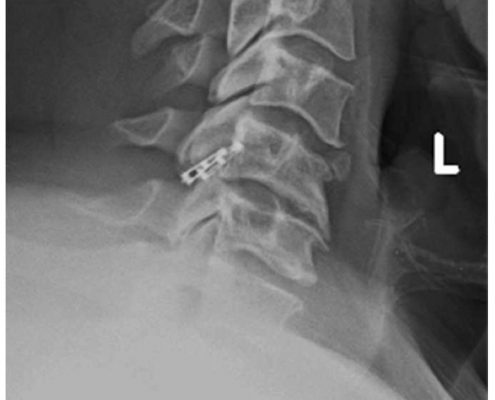

El sistema DTRAX® se compone de 2 cuñas de titanio que se introducen entre las facetas articulares cervicales para conseguir un aumento del espacio foraminal produciendo así la descompresión de la raíz o raíces nerviosas comprimidas a través de la distracción facetaria a la vez que produce una fijación estable de la articulación en el nivel implantado favoreciendo la fusión. Todo ello se realiza mediante un abordaje mínimamente invasivo gracias a un instrumental especialmente diseñado para ello.

DTRAX® está indicado para su uso en pacientes esqueléticamente maduros con patología degenerativa discal de la columna cervical (C3 a C7) con acompañamiento de radiculopatía y/o dolor facetario. La distracción facetaria que produce el DTRAX® hace que el espacio foraminal aumente aproximadamente en un 20% además de producir una estabilización de la articulación mayor en movimientos de rotación axial y movimientos laterales e igual en flexo- extensión si lo comparamos con la estabilización que produce una caja y una placa colocada mediante un abordaje anterior tradicional.

- Se mantiene la lordosis fisiológica del paciente.